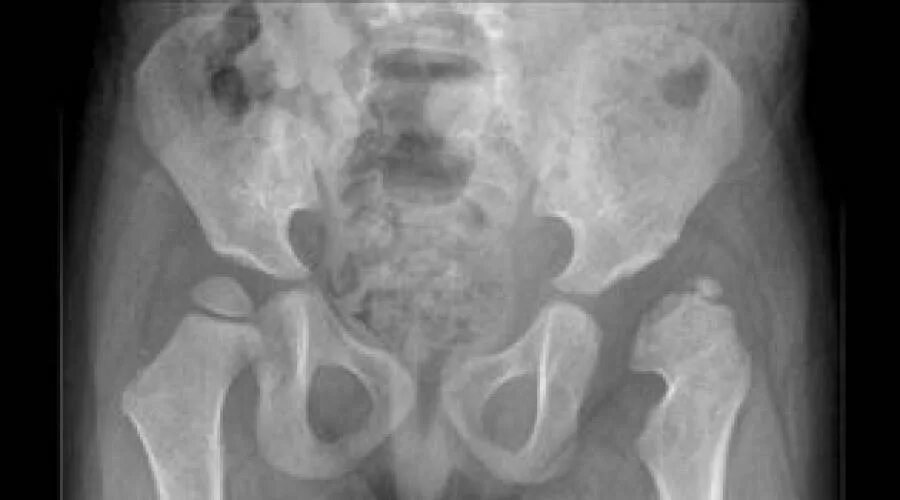

Вывих тазобедренного у взрослых